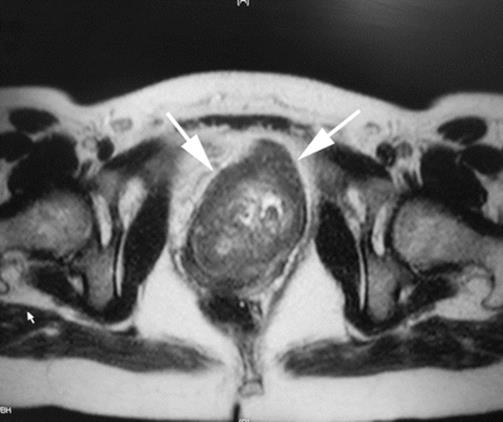

Fig. 8.44

An axial MRI shows the replacement and displacement of the urethra by the large mass. Multiple areas of necrosis are seen. The arrows outline the tumor